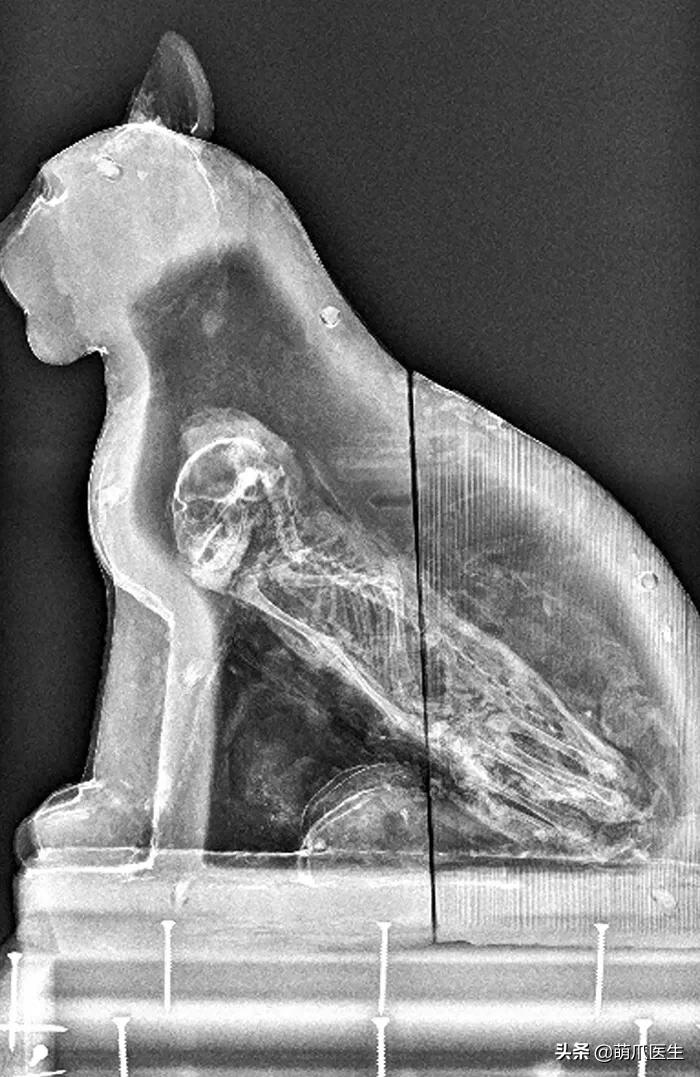

甚至还能发现长眠在 埃及石棺里的猫乃伊 ……